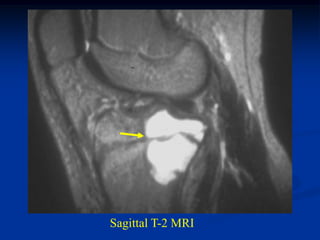

Case #608

17 year male with osteochondroma humerus

marrow

Axial T-1 MRI

cap

Sagittal T-1

MRI

Coronal T-2 MRI

Macro section